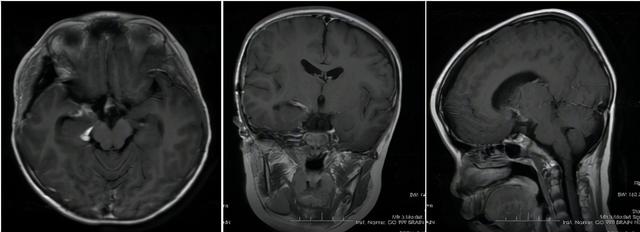

术后复查

近年来,儿童肿瘤人数逐年增加,已成为儿童死亡的第二大原因。颅咽管瘤是儿童常见的脑肿瘤,手术切除后预后良好。住院一段时间后,船又恢复了活力,没有任何后遗症,蹦蹦跳跳地出院了。